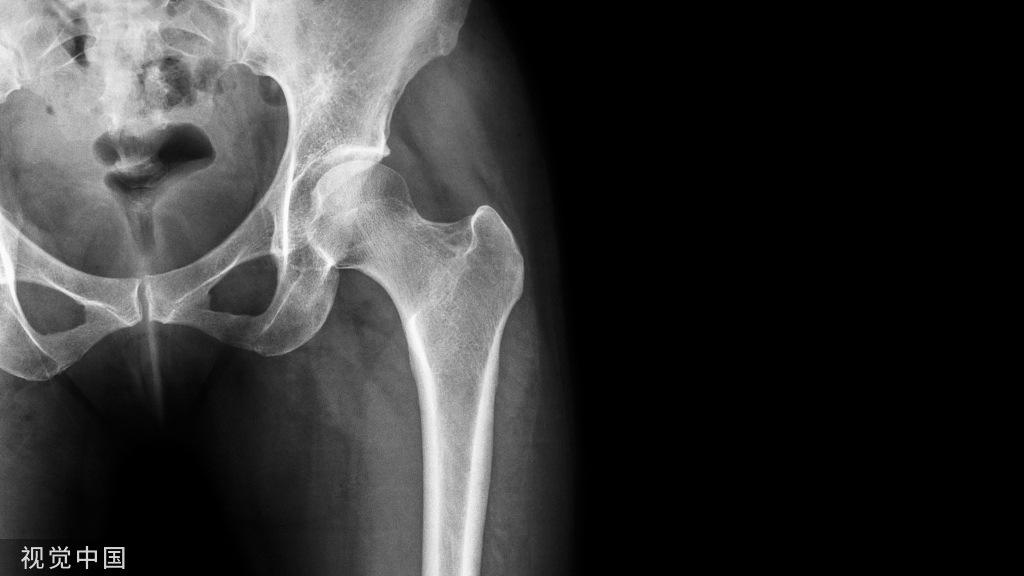

X线片检查

- 常规行正位、侧位、踝穴位

- 特殊位置:节内旋位、内斜位

- 应力位:前抽屉应力、距骨倾斜应力